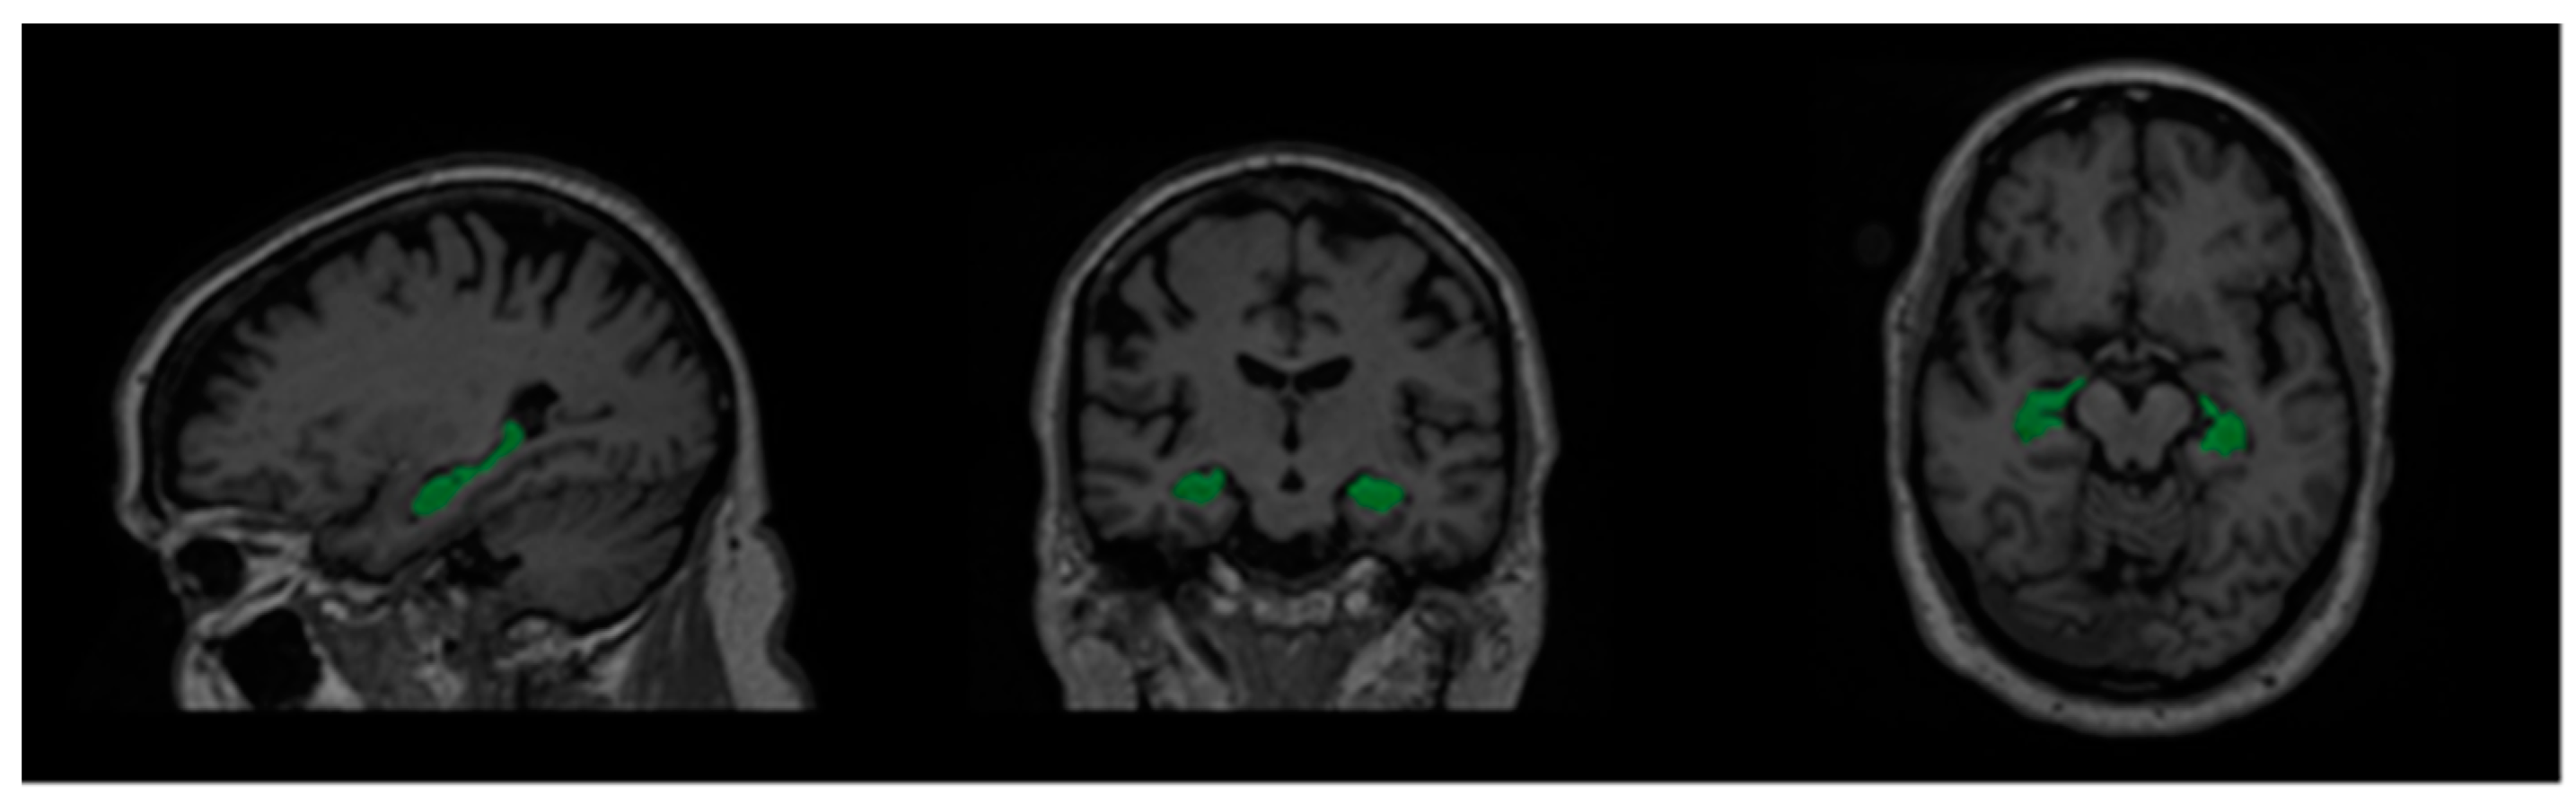

As mentioned above, 2D convolution models process volumetric MRI data by going through them slice-by-slice. In 3D MRI scans, there are three main orthogonal axes from which slices may be taken as shown in Figure 2. Therefore, most 2D convolution models adopt a multi-view approach in which they combine the outputs of several networks with different views to form a final predicted segmentation of the hippocampi.

Figure 2.

From left to right: sagittal, coronal, and axial view of an MRI volume. Left and right hippocampi are highlighted in green.